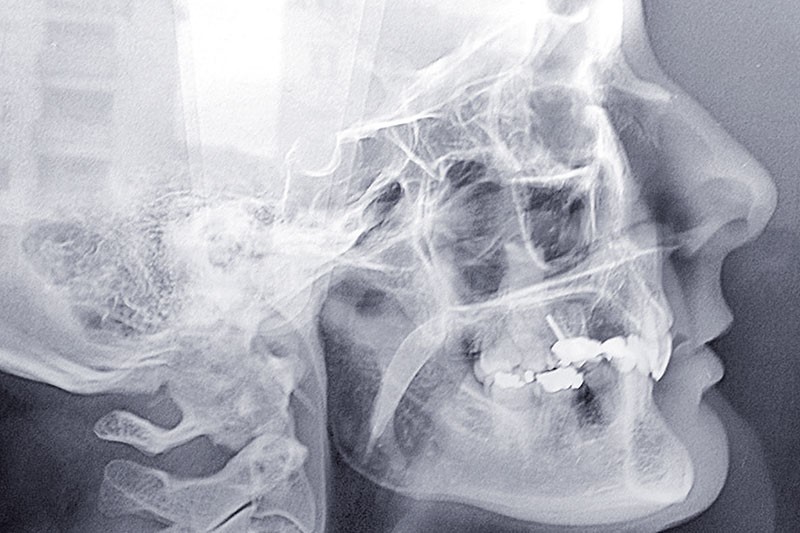

Malocclusion de classe II par rétrognathie mandibulaire dans un schéma squelettique hypodivergent (fig. 4 à 6).

Le plan de traitement prévu est donc la réouverture des espaces pour une solution prothétique implantoportée. La classe II sera corrigée par une chirurgie d’avancée mandibulaire.